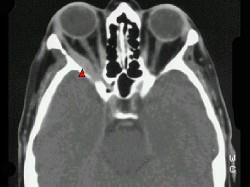

问题 对炎性假瘤(如图)治疗正确的是 ( )

选项 A、必要时手术完整切除防止复发 B、皮质激素用量宜少、短以避免全身并发症 C、一般局部用药效果好 D、放疗最敏感的是淋巴细胞浸润型 E、对皮质激素最敏感的是嗜碱性粒细胞

答案 D